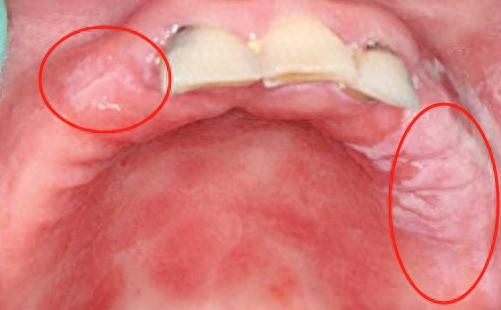

1、义齿性口炎

据统计,使用活动假牙,有三分之一的人容易患上义齿性口炎。主要表现为口腔粘膜出现亮红色水肿、黄白条索状、斑点状的假膜,佩戴者还会觉得存在口干、灼痛的感觉。